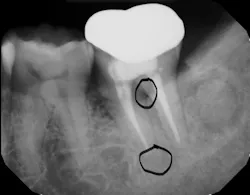

The periodontium surrounding the tooth can be a source of pain, especially if there is a concurrent periodontal lesion along with an endodontic lesion (figure 3). The tooth should be clinically examined and radiographs taken following root canal treatment to evaluate both hard and soft tissue. Hard-tissue defects, such as intrabony defects and furcation involvement, can cause inflammation leading to tooth pain. In addition, soft-tissue recession can expose root surfaces, which can then lead to sensitivity and tooth pain. Food impaction, especially if the tooth is temporized, can also mimic tooth pain. Gingival irritation from the rubber dam clamp used during the root canal can simulate tooth pain, but it is usually temporary and can be alleviated with rinses or medicaments. Referral to a periodontist may be required for pain of periodontal origin.